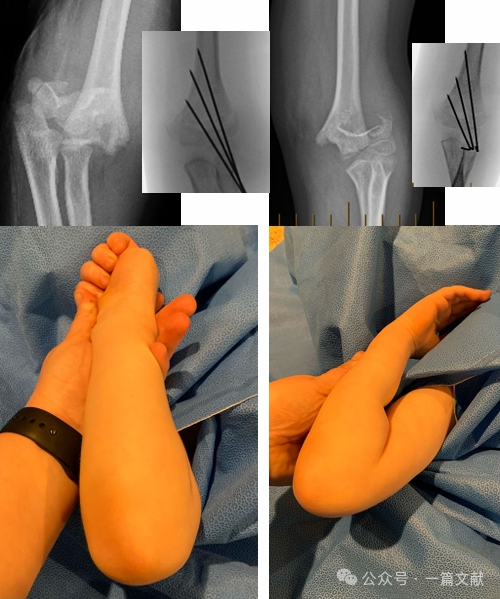

* Ideal Pin Placement Requirements: Use 1.5-2 mm K-wires. Pins should engage the medial and lateral columns with a divergent pattern. Greater separation between pins increases stability. As shown in the figure, pin configurations for Type 2A, 2B, and 3 fractures.

* Achieve wide separation at the fracture site.

* Pins should follow the metaphyseal flare to capture the lateral column.

* Laterally placed pins can be used to capture the medial column.

* Pin tips should engage the distal fragment just proximal to the fracture line.

* A third pin can be added between the two main pins for additional stability.

VI. Postoperative Management:

To prevent complications from postoperative swelling, a cast with a cut-out (as depicted) can be utilized.

K-wires are typically removed 3-4 weeks postoperatively.